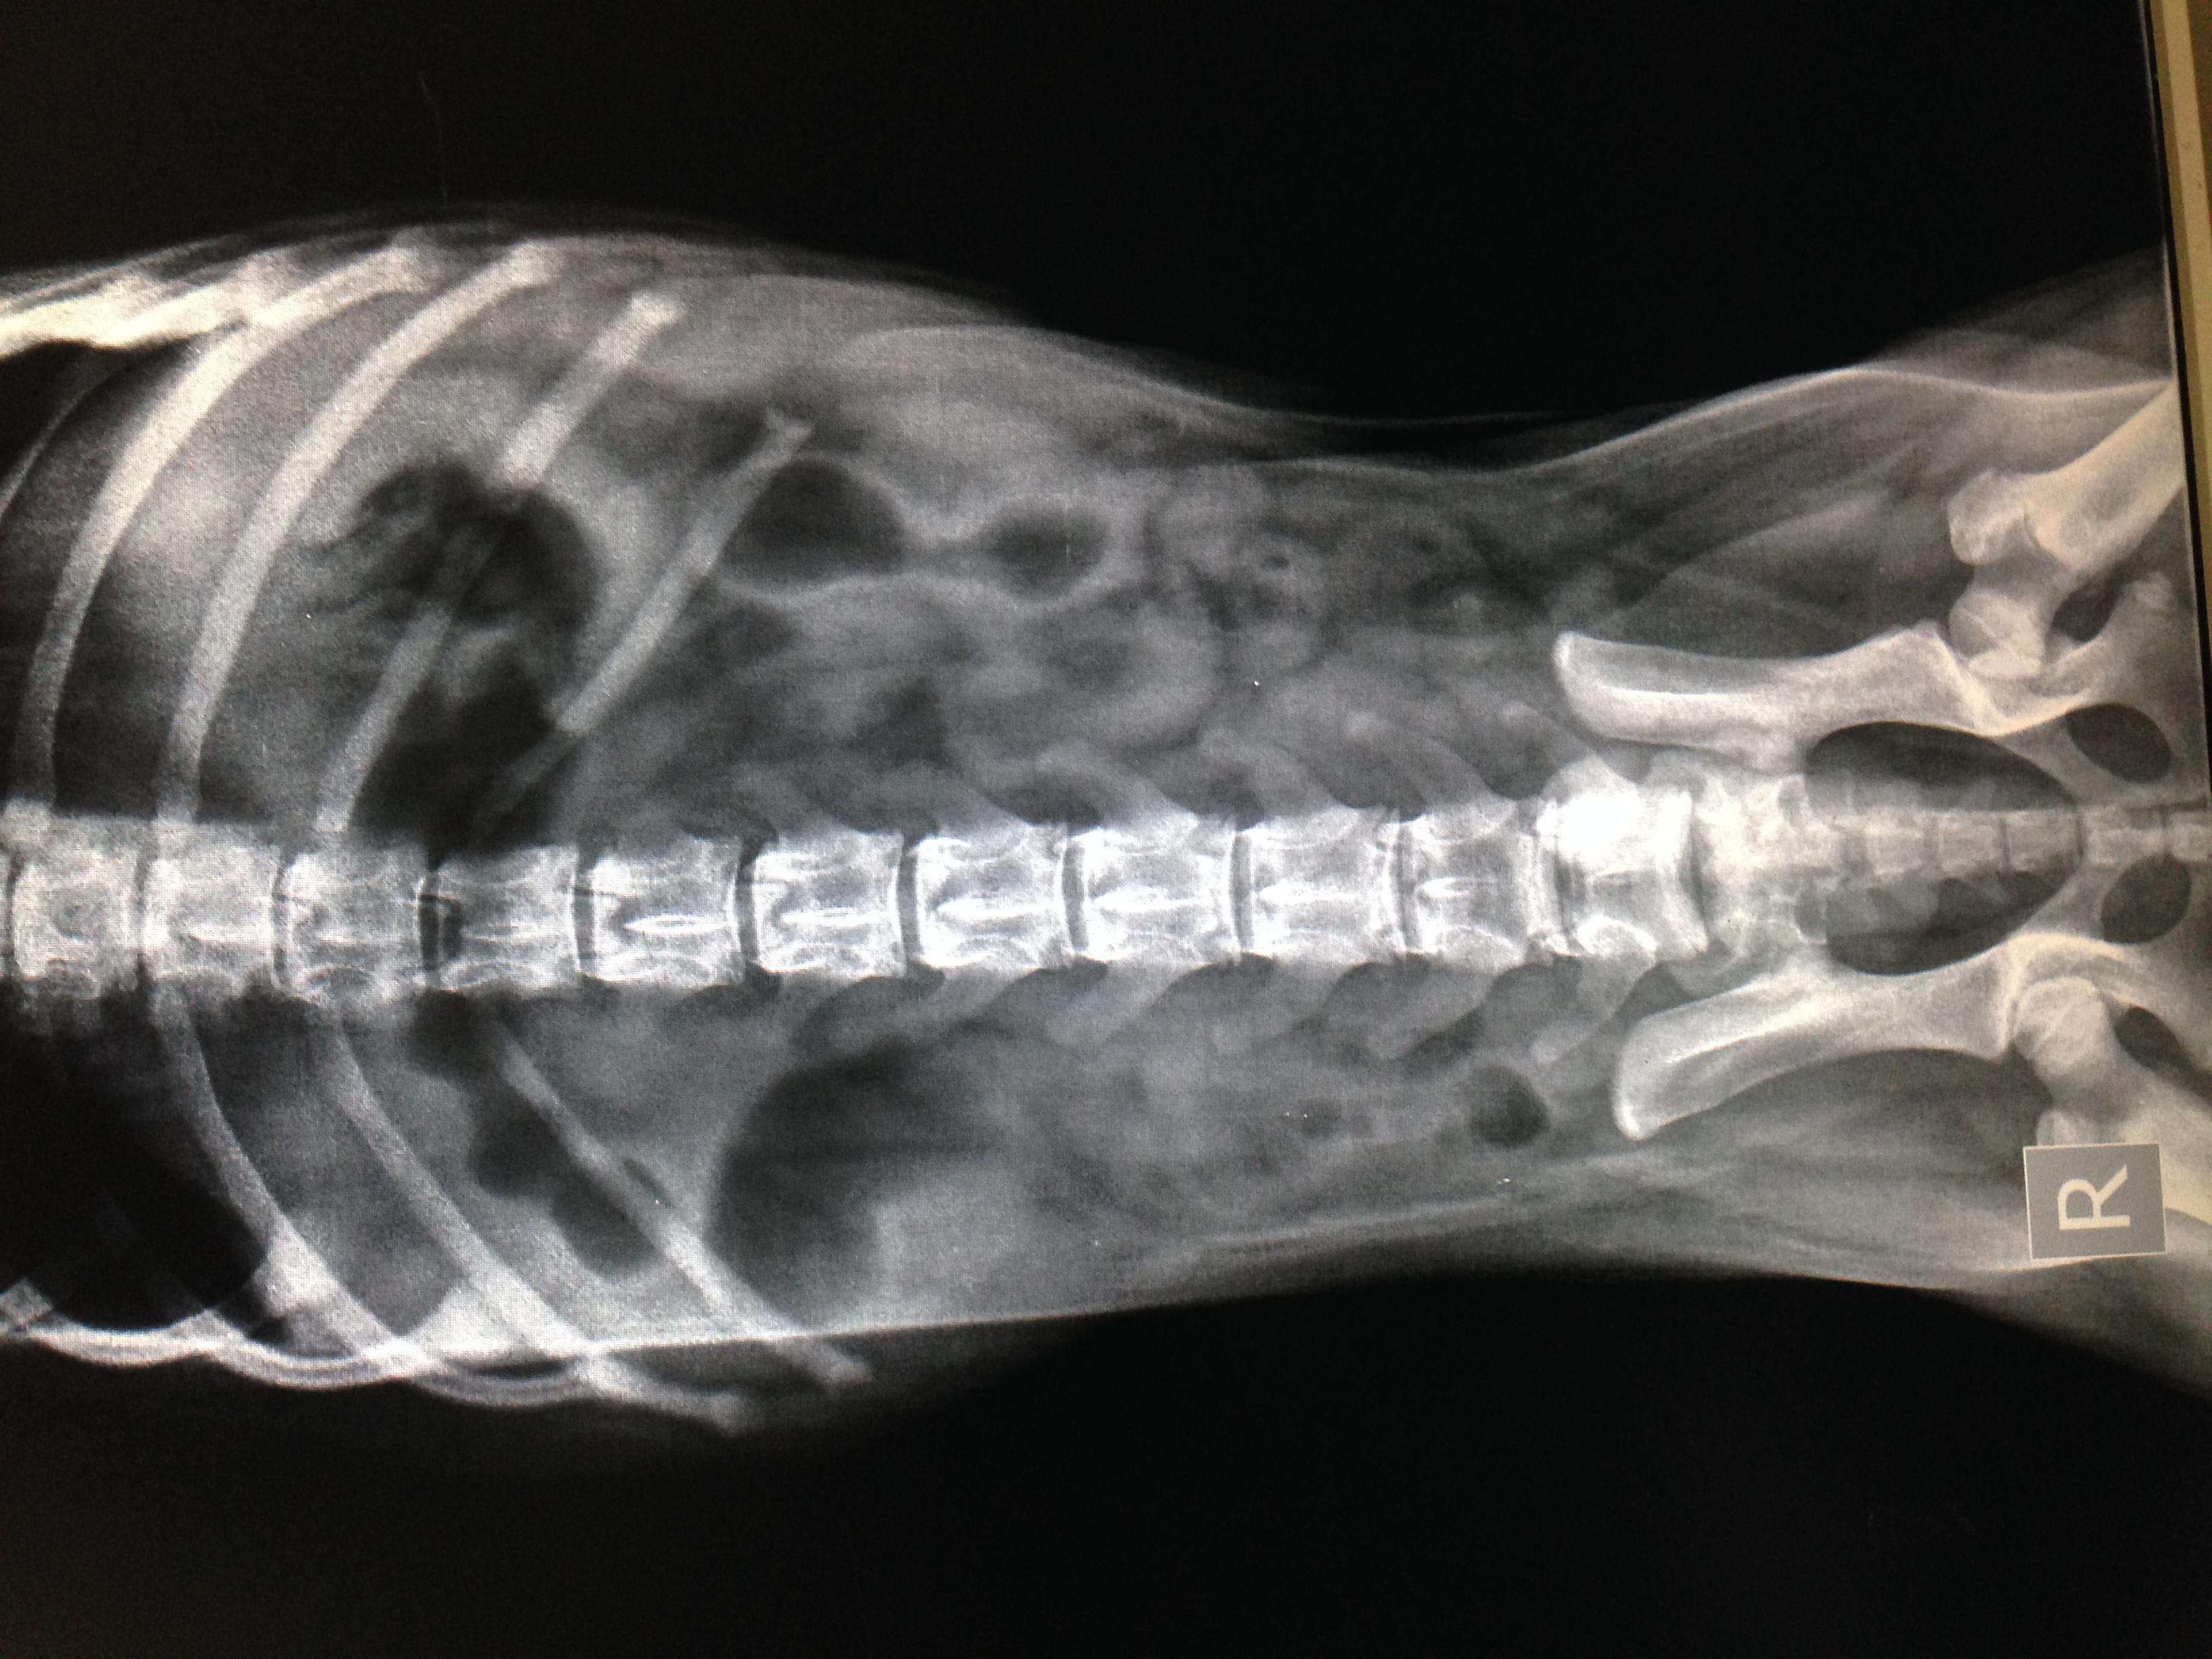

Common causes of bloody vomiting or diarrhea in a puppy include dietary intolerance, dietary indiscretion, intestinal parasites, GI blockage, toxic exposure, gastroenteritis, bacterial or viral (like parvo or distemper) infection, among others. The x-rays you provided are not diagnostic for any specific disease, but there are a couple large pockets of gas that could indicated GI blockage or a decrease in movement of the intestines, called ileus, Other diagnostics that can be performed are CBC, chemistry, parvo test, intestinal parasite screen, or coagulation profile. If you have additional diagnostic results, you can choose a one-on-one consult and we can discuss them fully and help you decide what else can be discussed with your vet.